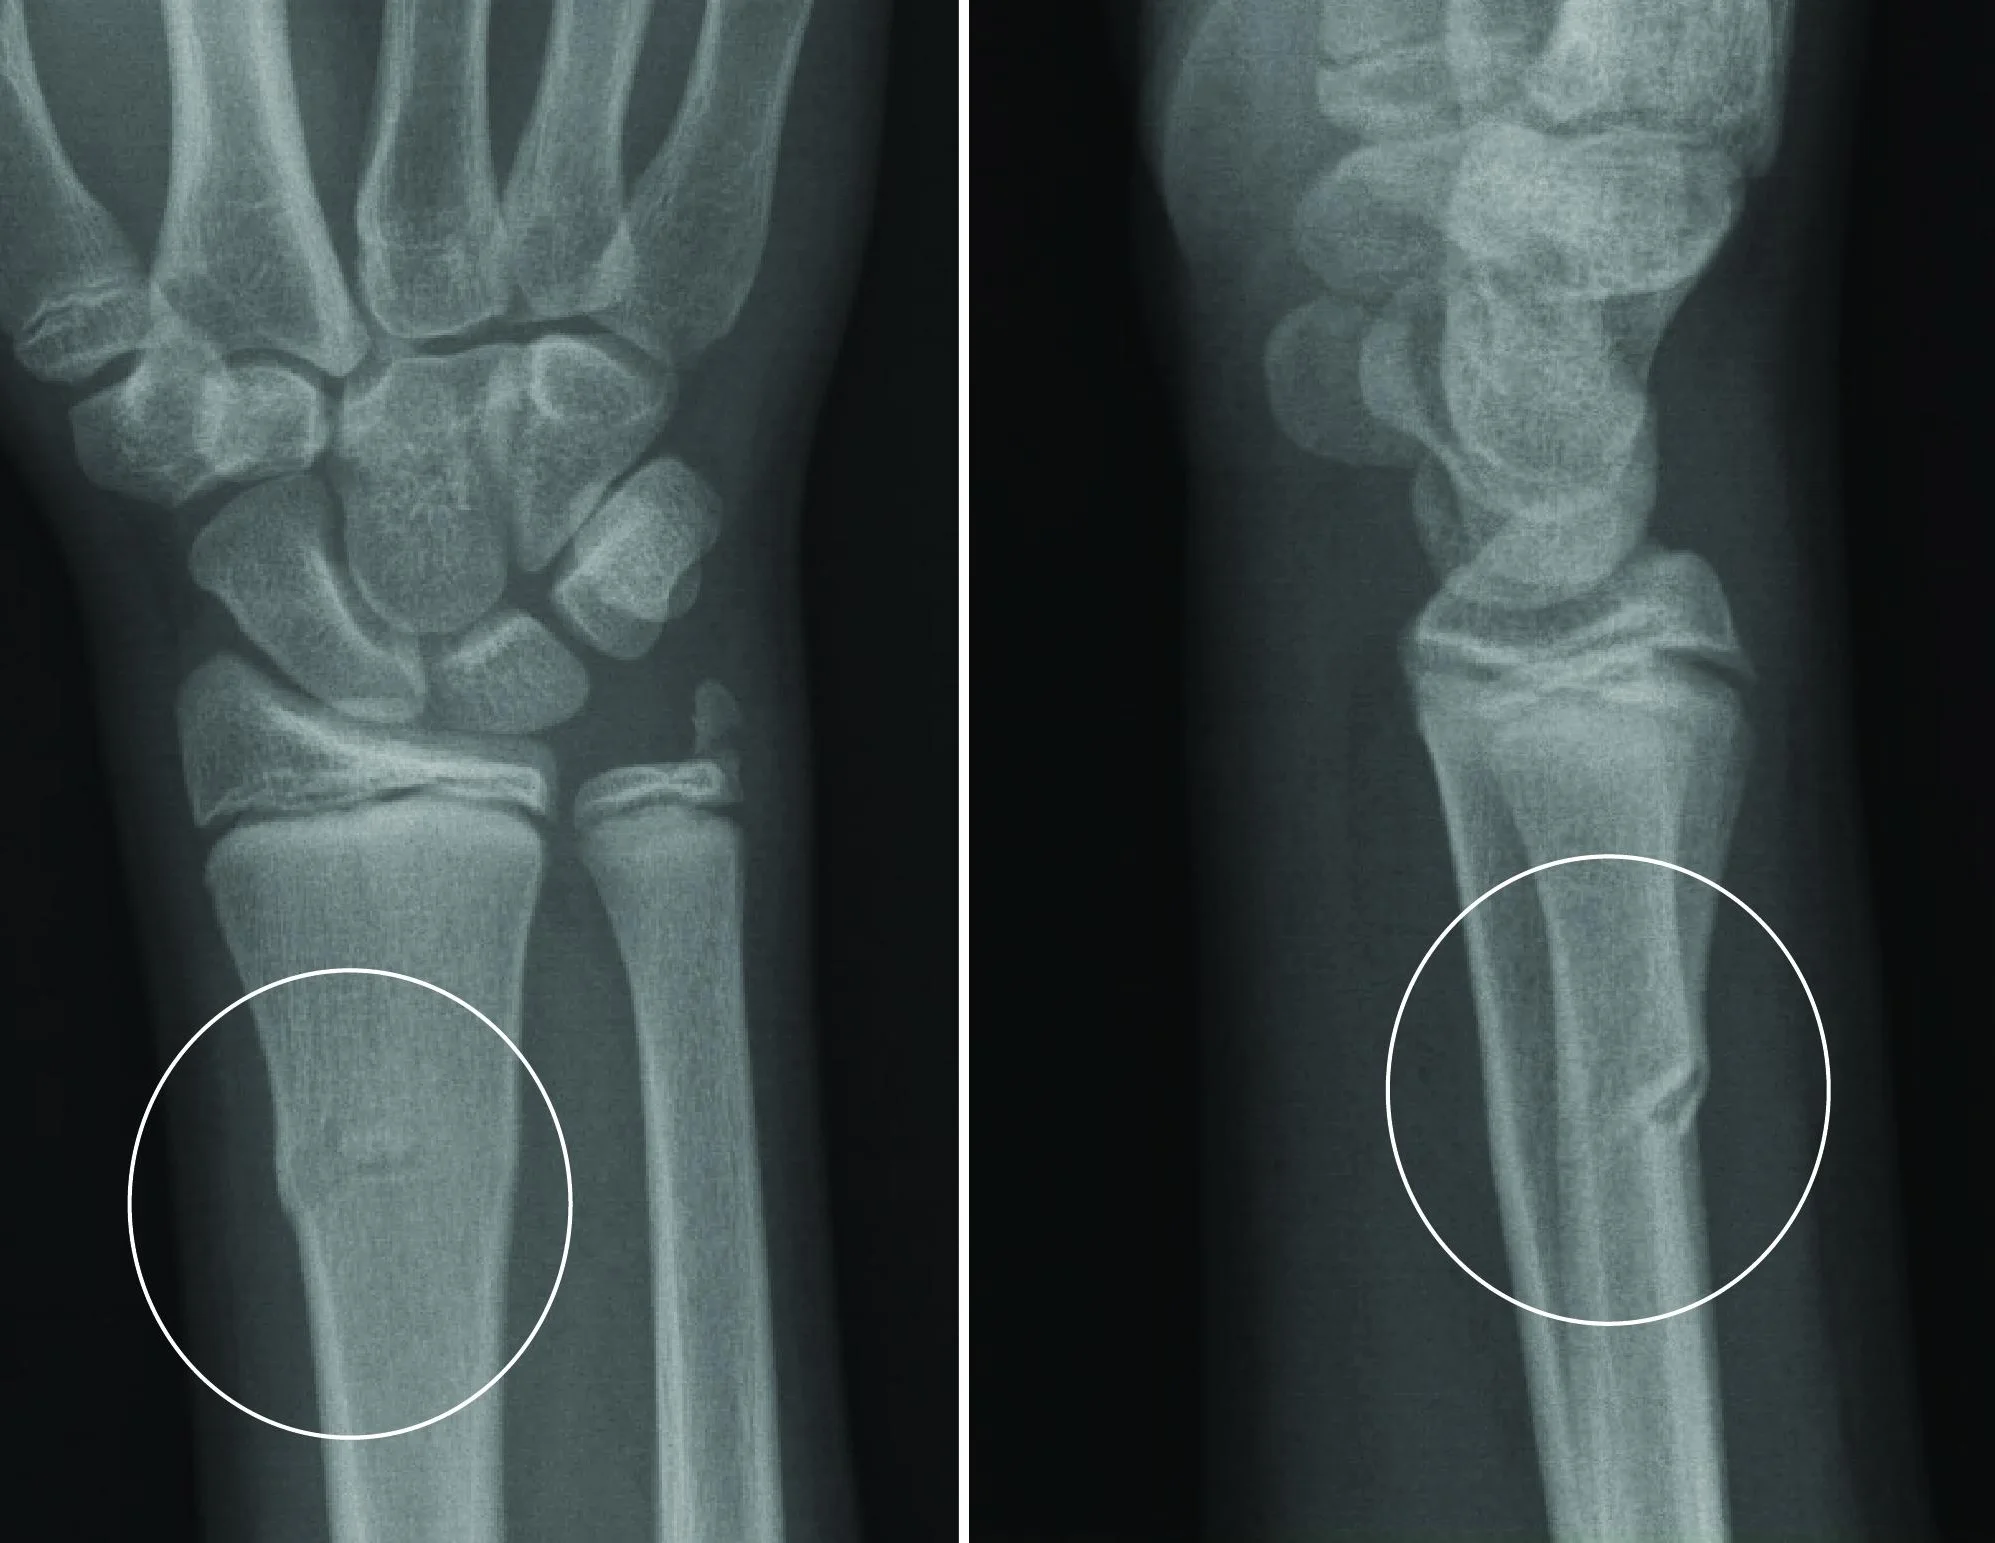

Buckle Fracture Raleigh Hand Surgery — Joseph J. Schreiber, MD

Distal Radius Fracture Raleigh Hand Surgery — Joseph J. Schreiber, MD